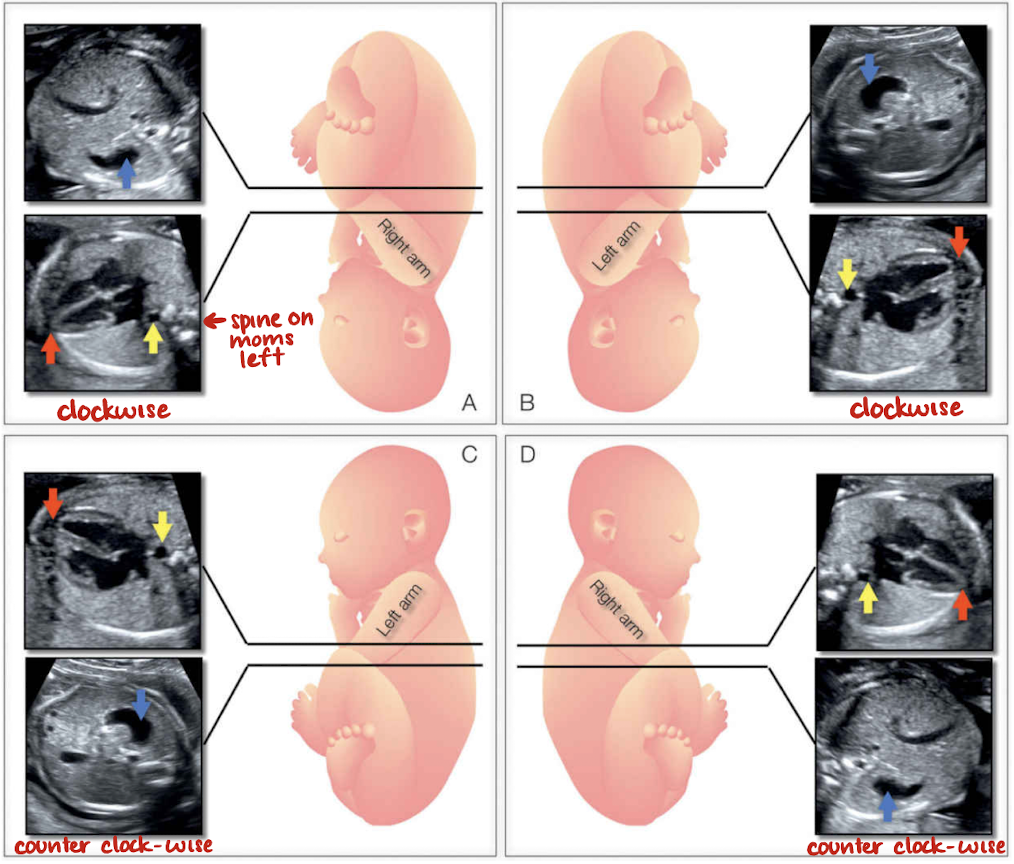

fetal lie

determine fetal lie and rotation

used to ensure heart is. incorrect position and orientation

fetal lie:

vertex

breech

transverse

fetal rotation:

supine

prone

RT/LT side up or down